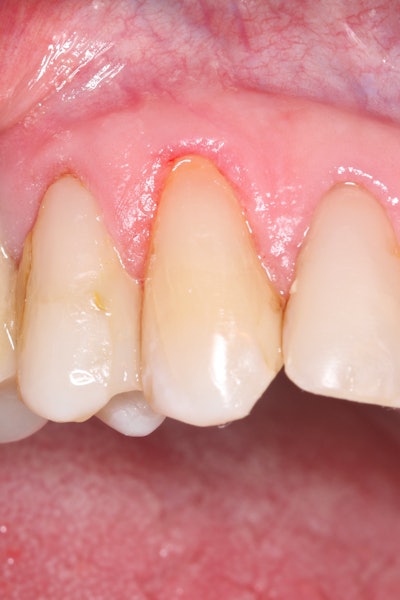

Clinical examination confirmed the presence of a small lesion and sensitivity, likely due to exposed dentin (Figure 1). There were no signs of pulpal involvement.

Figure 1: Initial presentation of tooth #6 showing the class V lesion with dislodged previous restoration and exposed dentin. Images and captions courtesy of Kuraray Noritake Dental Inc.Figure 1: Initial presentation of tooth #6 showing the class V lesion with dislodged previous restoration and exposed dentin. Images and captions courtesy of Kuraray Noritake Dental Inc.